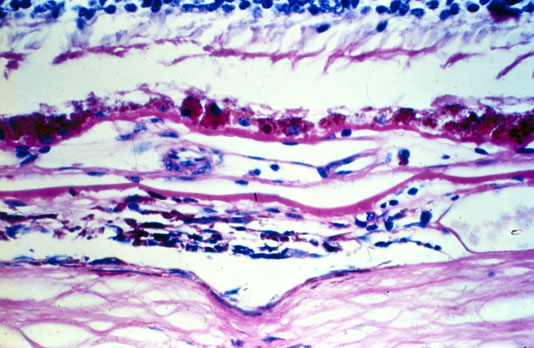

Figure 12. Occult choroidal neovascularization

B. Late staining plaque corresponds to an area of CNV located between BlamD with RPE and the remainder of Bruch's membrane.

C. One of 6 sources of neovascularization from the choroid.